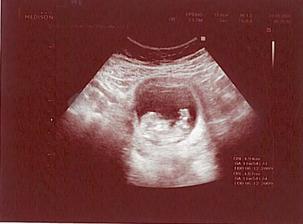

... 10.7. KO dopadla dobře .. prcek seděl v tureckém sedu a MUDr. řekl, že je to 1:0 pro kluka ... tak pravděpodobně čekáme Vikiho 🙂 ... 23.7. jdu na echo plodu a 31.7. na velký UTZ .. už se těším !!!

...23.7. echo plodu je bez známek kritických srdečních vad 🙂 ... potvrdili nám kluka a tatínek se byl na Viktorka podívat

... 31.7. jsme byli na velkém UTZ a byla se na Viktorka podívat i babička .. pěkně na ní otvíral pusinku, ale pindíka ukázat nechtěl, prý když nám doktor řekl, že to bude chlapeček, tak to tak bude .. měl pořád kolínka u sebe, lumpík jeden